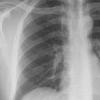

Normal PA Male

Date: 12/06/2014

Views: 6528